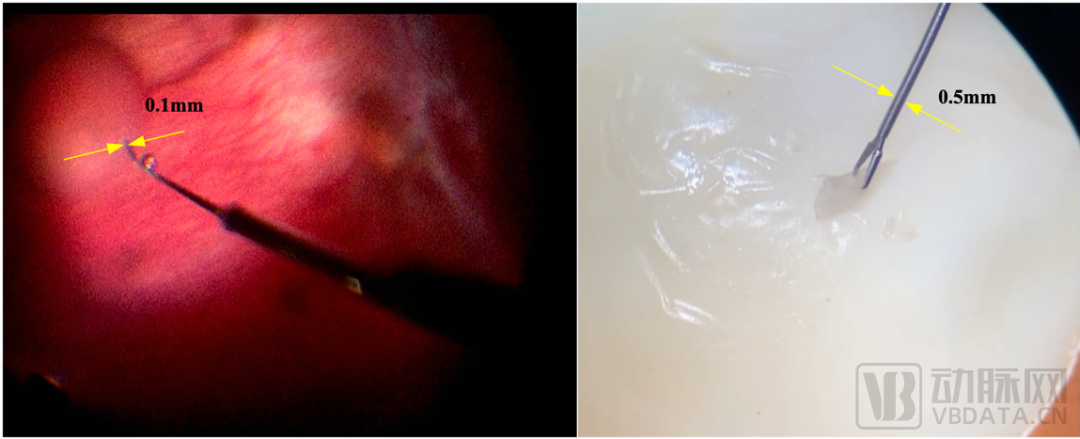

據(jù)悉,迪視醫(yī)療布局研發(fā)的顯微外科手術(shù)機(jī)器人擁有近20個(gè)超高自由度,能夠輔助顯微外科醫(yī)生完成各種高難度、超顯微精細(xì)靈巧操作,例如吻合直徑范圍為0.3~0.8毫米的淋巴管、血管或者神經(jīng),在耳鼻喉、淋巴外科、神經(jīng)外科、整形外科等多科室均有重大應(yīng)用價(jià)值。

圖左:醫(yī)生操控迪視機(jī)器人用于活體兔視網(wǎng)膜下腔注射;圖右:醫(yī)生操控迪視機(jī)器人用于20μm厚的雞蛋薄膜剝離